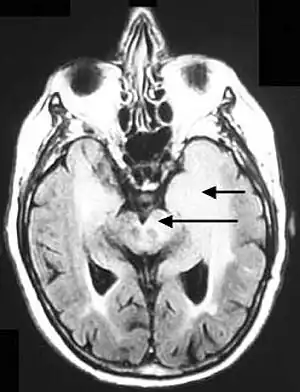

Axial fluid-attenuated inversion recovery MRI image demonstrating tumor-related infiltration involving lenticular nuclei (Arrow).

Axial fluid-attenuated inversion recovery MRI image demonstrating tumor-related infiltration involving both temporal lobes (Short arrow), and the substantia nigra (Long arrow).